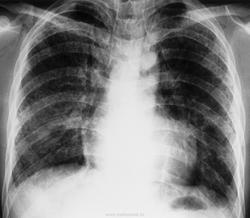

Пациент, будучи в нетрезвом состоянии взял паракват в рот, и затем выплюнул.

Отравления при вдыхании параквата.

Паракват - это гербицид, который используется в сельском хозяйстве во многих странах.